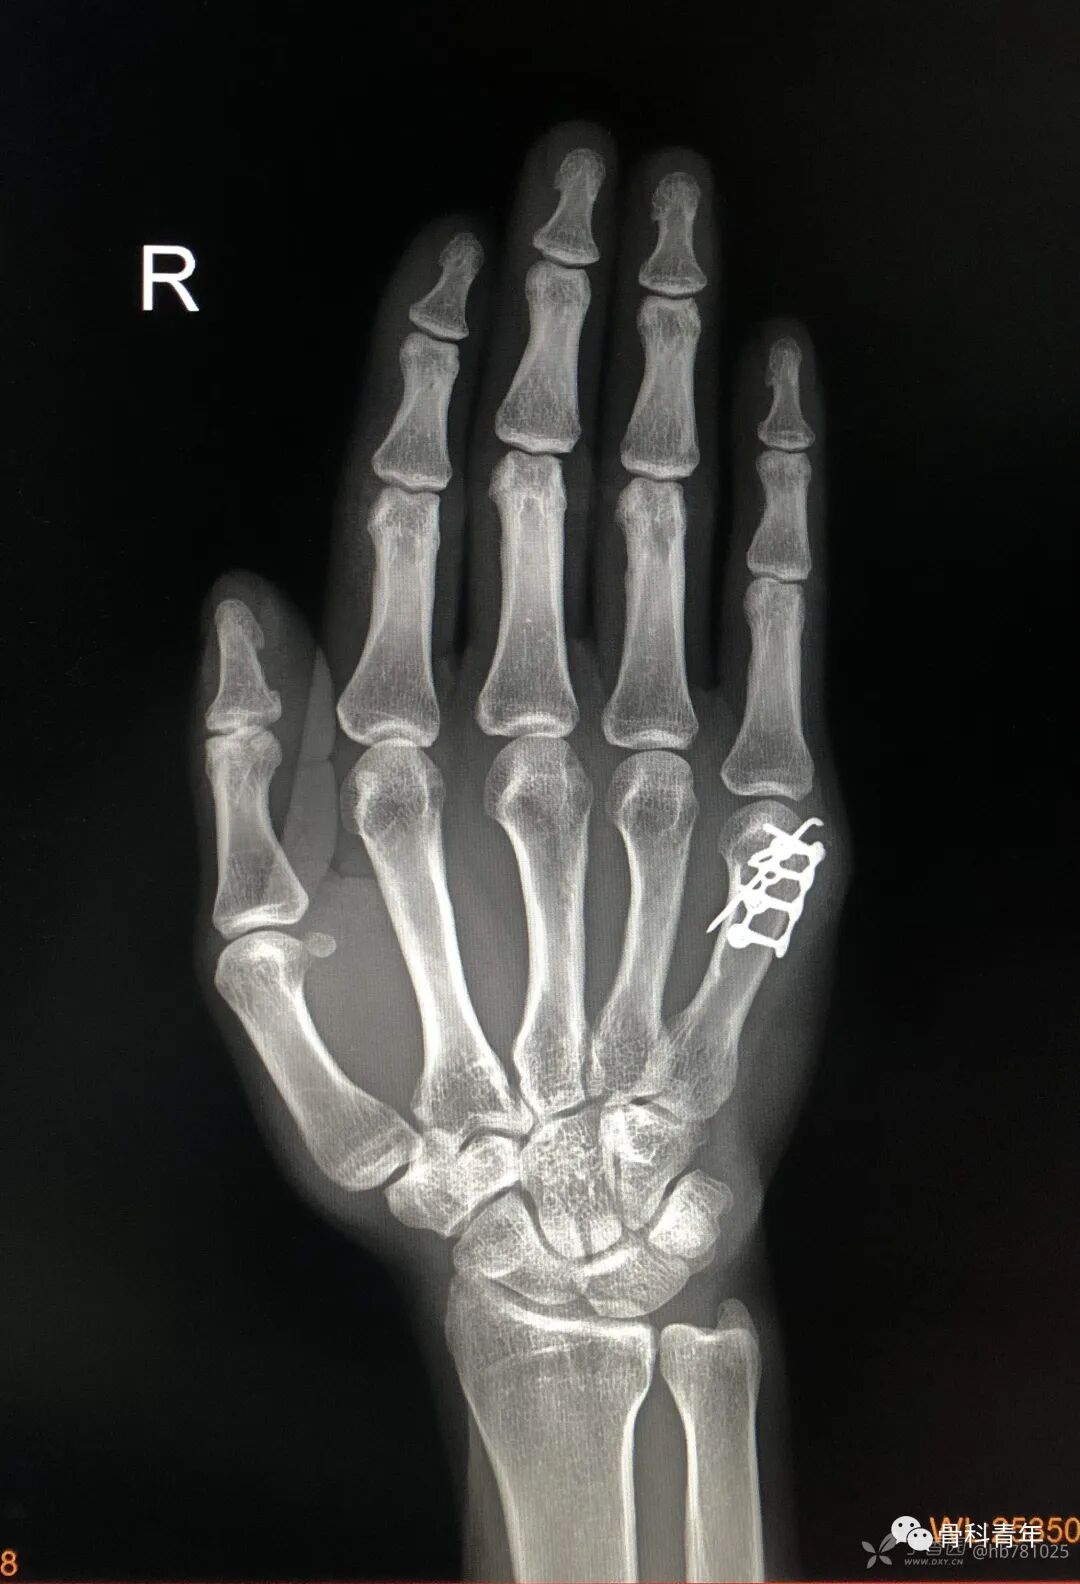

28.掌骨头骨折